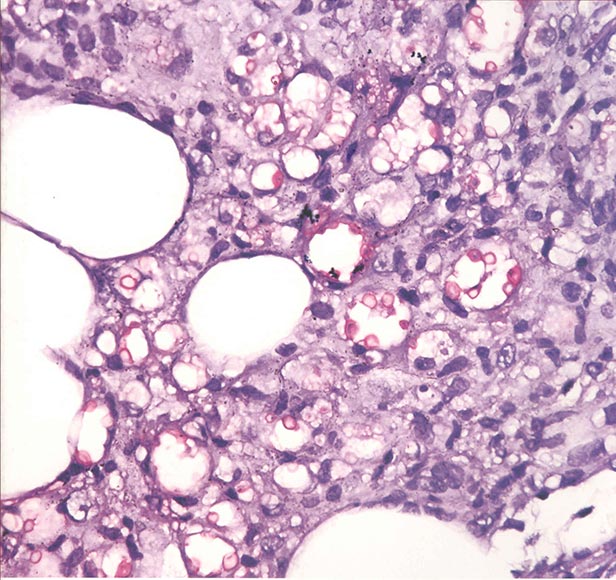

Haga usted el diagnóstico. Parte 1

Haga usted el diagnóstico. Parte 2